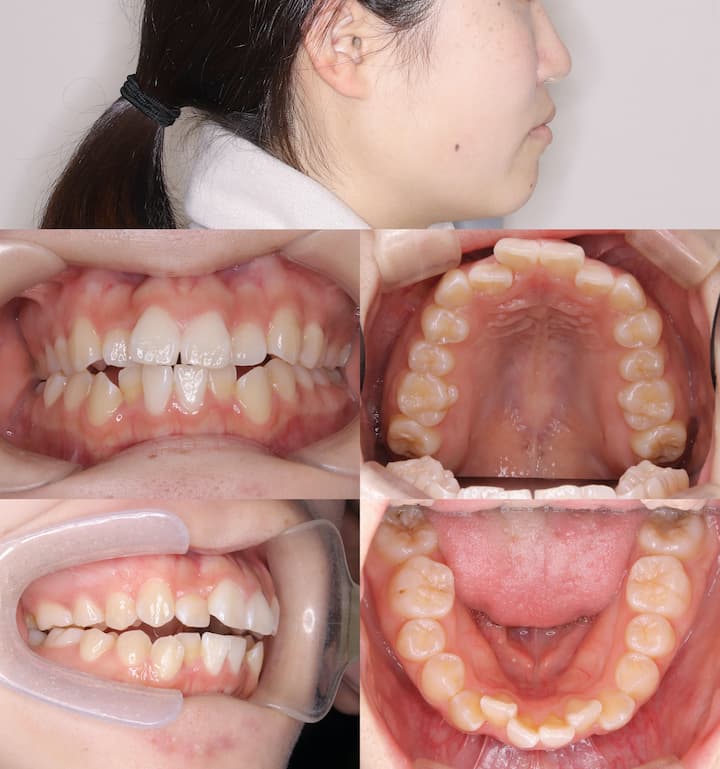

初診時年齢:27歳2ヶ月居住地:大阪市内

主訴:歯列不正および口唇部の突出感

診断所見

初診時の口腔内所見および頭部X線規格写真分析より、以下の所見が認められました。・上下顎前歯部の叢生

・口唇部の突出感

・AngleⅠ級臼歯関係(良好な臼歯関係)

・下顎骨の後方位(ハイアングル症例)

・下顎下縁平面角の増大